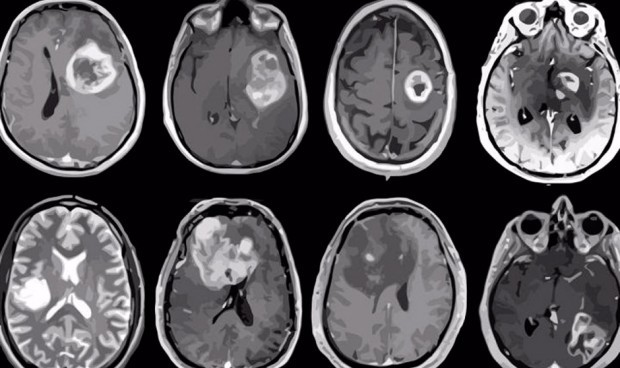

Una nueva vacuna de ARN mensajero fabricada en la Universidad de Florida contra el cáncer ha permitido reprogramar el sistema inmunológico del humano para poder atacar al tumor cerebral más agresivo de todos, el glioblastoma. Este nuevo abordaje ya se ha testado en un ensayo clínico en humanos, concretamente con cuatro pacientes adultos, logrando un resultado más que prometedor.

Una de las principales novedades de la vacuna es que usa células tumorales propias del paciente, con el fin de crear una vacuna personalizada. El principal resultado cosechado hasta la fecha es que la vacuna permitió estimular una respuesta del sistema inmunológico del paciente para contraatacar el tumor.